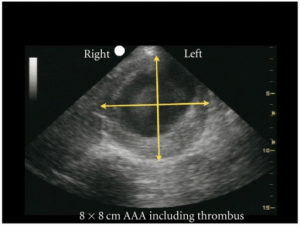

- AAA identified when diameter measured from outer wall to outer wall (including mural thrombus if present) is >3cm

- Measurements should be done in a transverse view of the aorta for best wall to wall measurement

- Avoid oblique measurements which can be falsely large

- Mural thrombus can cause falsely small measurements